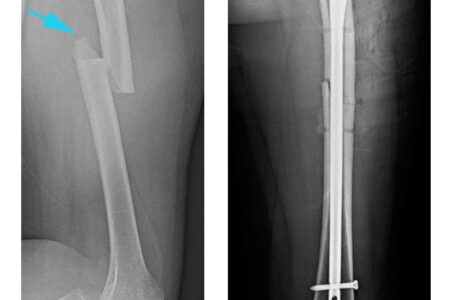

Femur Femoral Shaft Fracture Physiotherapy

19 November 2025

Physiotherapy for Femur Fractures

Read more